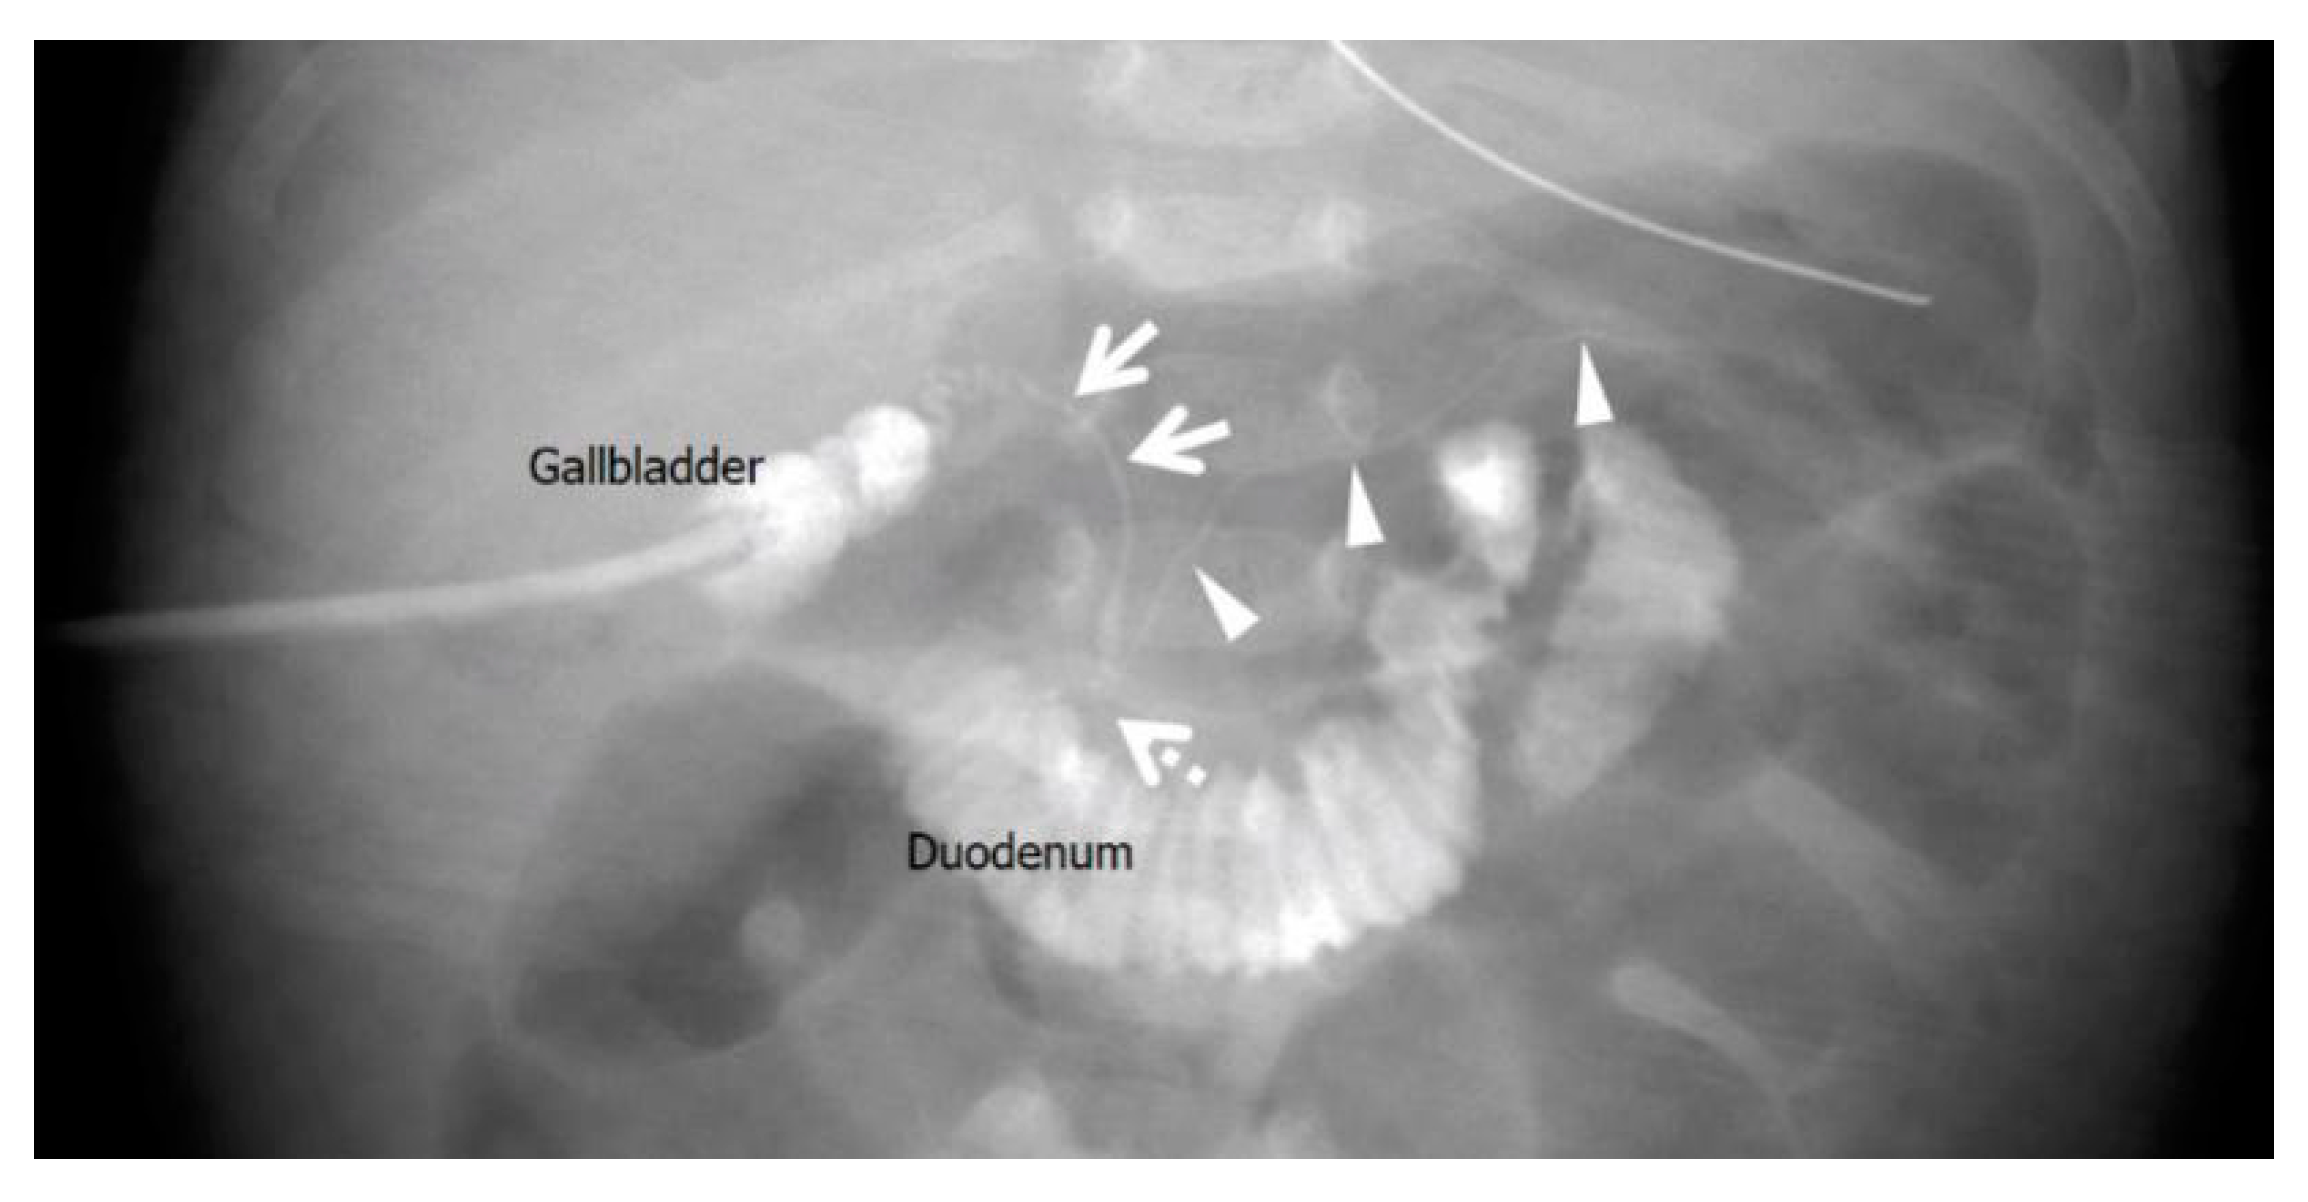

2.1. Case 1: 4-Day-Old Boy